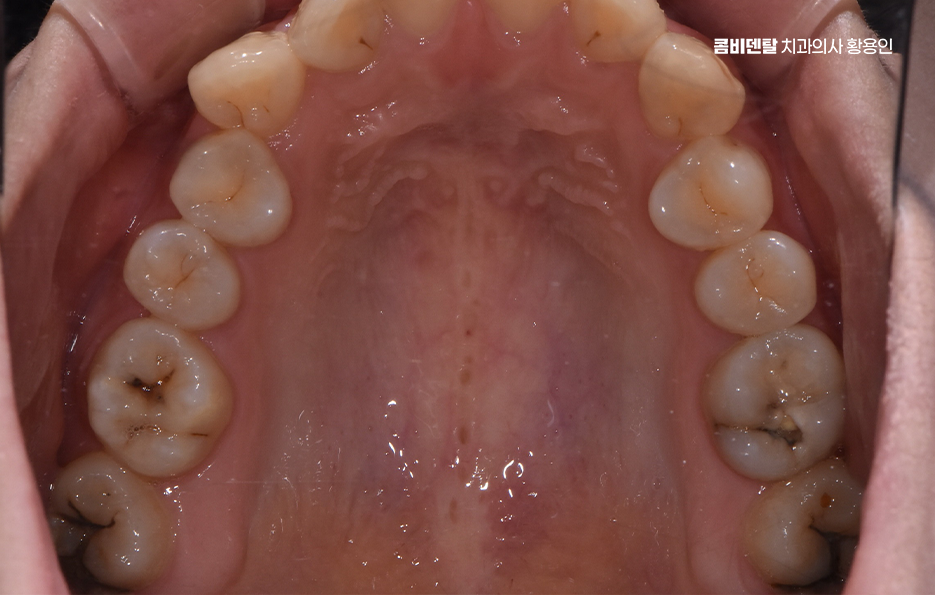

치료는 앞니 같이 신경관 수가 적고 간단한 경우에는 12번으로 끝나는 경우도 있지만, 염증이 심하거나 근관 구조가 복잡한 경우엔 34회 정도에 걸쳐 진행되기도 하며 특히 어금니처럼 뿌리가 여러 갈래로 갈라진 치아는 신경이 얇고 구불구불한 경우가 많아서, 그만큼 정밀하게 소독하고 약재를 채워 넣어야 하기 때문에 시간이 더 걸릴 수 있어요.

이 과정에서 중요한 건 근관 내부를 완전히 소독한 후, 안쪽에 약재를 채워서 다시 세균이 침투하지 않게 밀봉하는 거예요. 이걸 제대로 하지 않으면 시간이 지나면서 2차 감염이 생기고, 다시 신경치료를 해야 하거나, 결국 발치까지 가게 되는 경우도 있어서, 처음 치료가 정밀하게 이뤄지는 게 무엇보다 중요하며 근관치료가 완료되면 그 위에 보강재를 넣고, 크라운을 씌워 치아를 보호하게 되는데 신경을 제거한 치아는 수분과 영양 공급이 끊어져서 점점 약해지고 깨지기 쉬워지기 때문에 신경치료 후에는 크라운을 씌우는 것이 수순이라 할 수 있어요